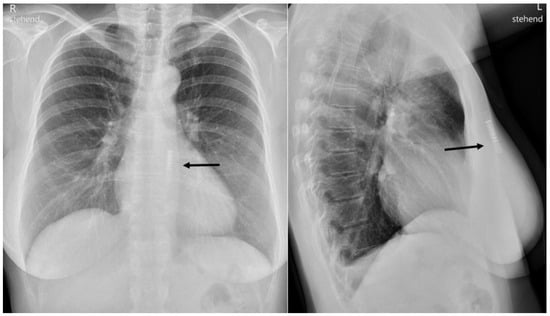

Figure 4. The X-Ray shows the ILR parallel to the left sternal border. The silicone breast implants are hardly visible.

A chest X-ray performed at a later stage for other reasons revealed the device to be located as initially intended (Figure 4). The following weeks were uneventful, the scar healed nicely (Figure 5) and the patient did not complain of any device-related problems.